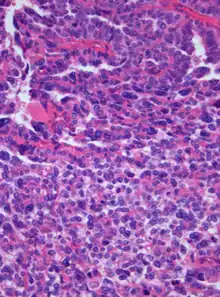

| Photomicrograph of hematoxylin-eosin stained section of a choroid plexus carcinoma (grade III WHO) at 400x magnification. | |